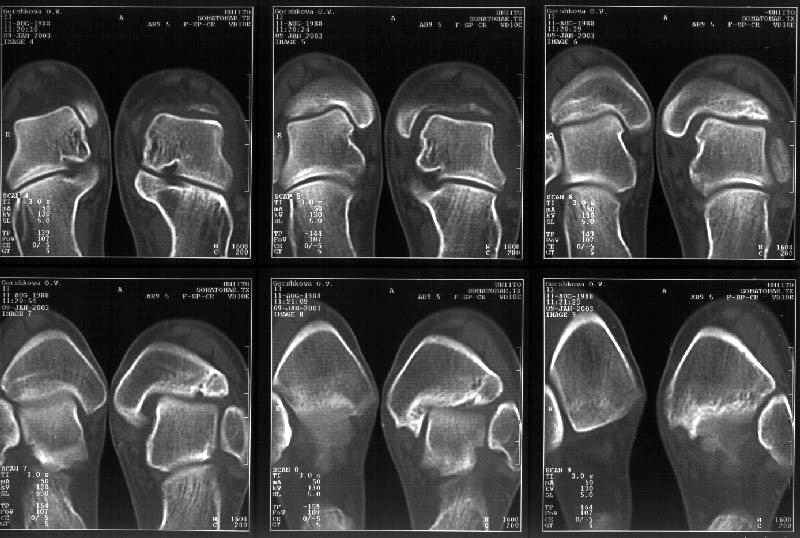

На следующий день пациентке сделали КТ. Может быть, после просмотра картинки будут другие предложения? Не убрать ли ве-таки этот фрагмент

позади внутренней лодыжки, который оттесняет таран кнаружи?

Думаю, КТ прочитан не верно. Задняя часть медиального маллеола, в сущности уже часть заднего маллеола стоит на месте и трогать её не следует. Передняя часть маллеола на 3-4 мм удалена от тарана. Сравните с пространством между

латеральным маллеолом и тараном. В норме все три должны быть одинаковы: между тараном и латеральным, задним и медиальным. Это главное условие устойчивого сидения тарана в голеностопном суставе.

Все-таки она как раз была была отколота и вместе с тараном смещена латерально.

Внутренняя лодыжка не была сломана, она как была на своем месте, так там и находится. Это таран от нее отдавлен кнаружи смщенным в его сторону фрагментом позади внутренней лодыжки. За счет чего и есть проявления нестабильности связок.

Вот и проблема. Восстанавливать ли эту равномерность сейчас, и если да, то как. Вот точка зрения коллеги из Штатов:

Interesting case. thanks for the ct cuts. now it is real clear that there is a posterior medial maleolar fragment displaced into the joint forcing the talus laterally. My first inclination in this young girl is to debride out the displaced fragment. The difficult part will be visualization ot know how much to take. My approach would be through an oblique medial malleolar osteotomy and hinge the distal malleolus away from the talus leaving the deep deltoid intact. this way you could easily view the whole articular surface of the medial gutter. I would debride the prominent bone back slightly beyond the level of the normal

malleolar surface. The osteotomy may also help reduce the widened mortise. I don't see anything i would do to the syndesmosis area nor any

significant lenght differences between the fibula and tibia laterally form the proximal tibia fracture.

Мне в тоже время совершенно ясно видно по той же КТ, по 4 срезам, расположенным в центре и вверху пленки, что перелома внутренней лодыжки не было, в следующем собщении я приложу увеличенный фрагмент томограммы. А к этому письму прилагаю увеличеный фрагмент послеоперационной рентгенограммы, где выделил отколотый фрагмент

позади внутренней лодыжки. И он, как я вижу, находится между стержнем и тараном. А перелома внутренней лодыжки, и тем более смещения, IMHO

не определяется.

Здесь 4 среза, начиная от основания лодыжки и проксимальнее. Где, по Вашему мнению, проходит линия перелома, отделяющая переднюю часть внутренней лодыжки от большеберцовой кости? Заранее спасибо.